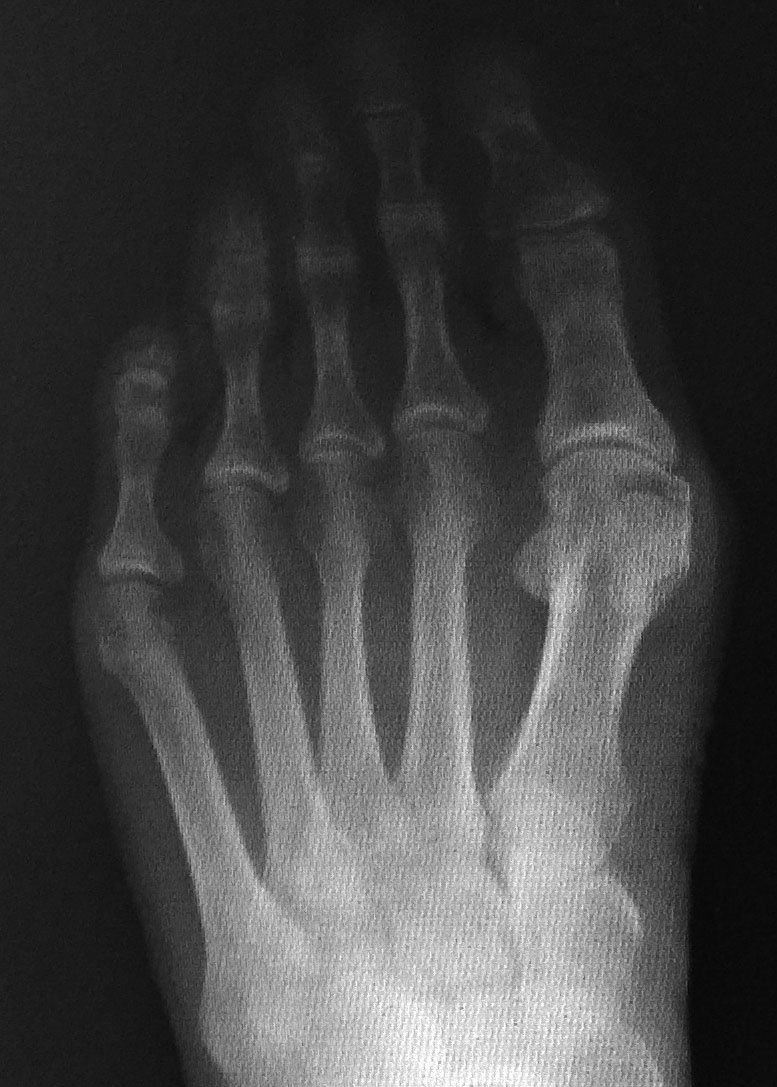

Hallux valgus

Bunions

The outwards drift of the great toe, associated with the formation of a bony lump on the inside of the great toe joint.